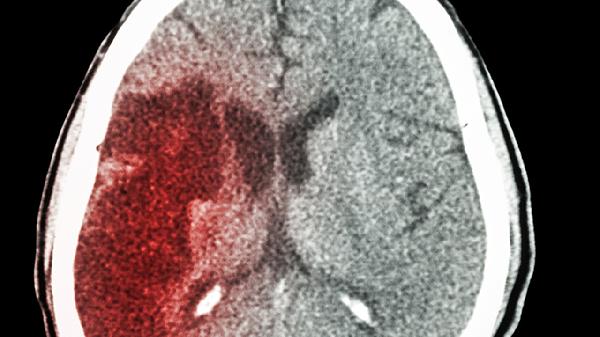

腦出血保守治療主要包括臥床休息、控制血壓、降低顱內壓、預防并發(fā)癥及營養(yǎng)支持等措施。腦出血通常由高血壓、腦血管畸形、凝血功能障礙等因素引起,可能伴隨頭痛、嘔吐、意識障礙等癥狀。建議及時就醫(yī),在醫(yī)生指導下進行規(guī)范治療。

保守治療期間需密切監(jiān)測意識瞳孔變化,定期復查頭顱CT觀察血腫吸收情況。恢復期應進行肢體功能康復訓練,控制血壓低于130/80mmHg。飲食選擇低鹽低脂高蛋白食物如魚肉、雞蛋白、西藍花等,避免辛辣刺激性食物。保持情緒穩(wěn)定,6個月內禁止重體力勞動和劇烈運動。